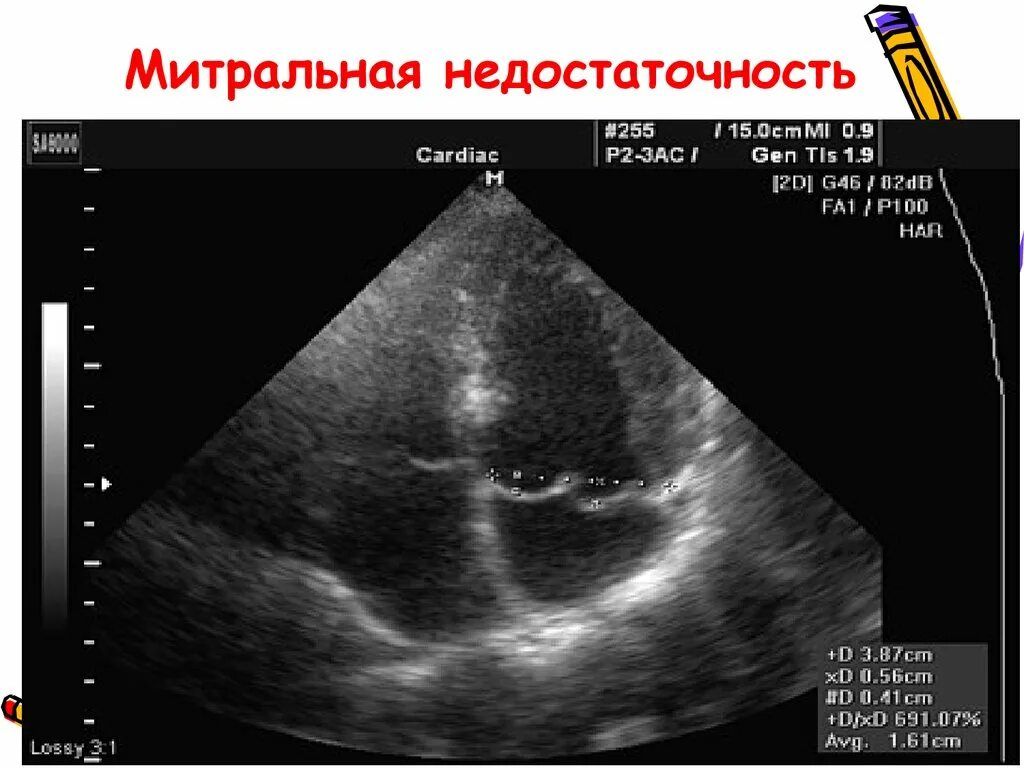

Узи сердца показывает сердечную недостаточность